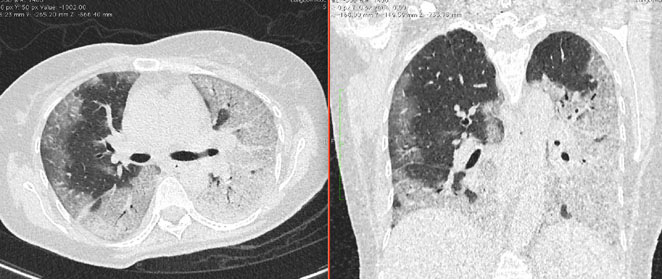

4.3. ЛУЧЕВАЯ ДИАГНОСТИКА COVID-19

Методы лучевой диагностики применяют для выявления COVID-19 пневмоний, их осложнений, дифференциальной диагностики с другими заболеваниями легких, а также для определения степени выраженности и динамики изменений, оценки эффективности проводимой терапии.

К методам лучевой диагностики патологии ОГК пациентов с предполагаемой/установленной COVID-19 пневмонией относят:

- Компьютерную томографию легких (КТ),

КТ имеет высокую чувствительность в выявлении изменений в легких, характерных для COVID-19. Применение КТ целесообразно для первичной оценки состояния ОГК у пациентов с тяжелыми прогрессирующими формами заболевания, а также для дифференциальной диагностики выявленных изменений и оценки динамики процесса. КТ позволяет выявить характерные изменения в легких у пациентов с COVID-19 еще до появления положительных лабораторных тестов на инфекцию с помощью МАНК. В то же время, КТ выявляет изменения легких у значительного числа пациентов с бессимптомной и легкой формами заболевания, которым не требуется госпитализация. Результаты КТ в этих случаях не влияют на тактику лечения и прогноз заболевания при наличии лабораторного подтверждения COVID-19. Поэтому массовое применение КТ для скрининга асимптомных и легких форм болезни не рекомендуется.

15. Рекомендации по формированию описаний и оценке изменений в легких и ОГК при имеющейся/подозреваемой пневмонии COVID-19 представлены в Приложении 1.